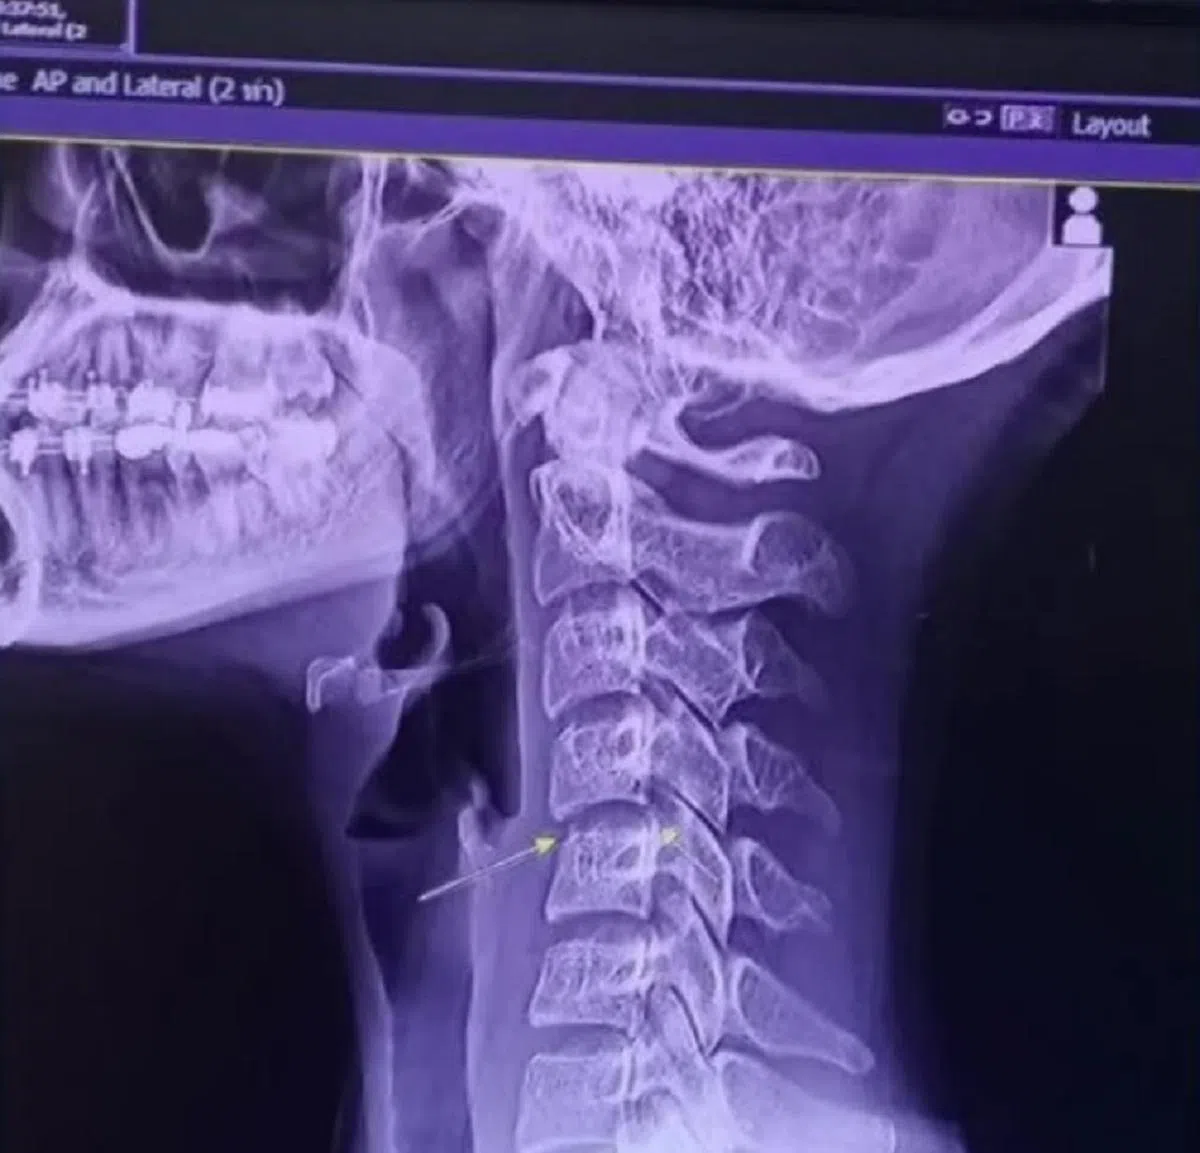

查亚达的X光片显示,按摩师的“颈部扭动”护理导致她的颈椎严重受损。(Chayada Prao-hom脸书)